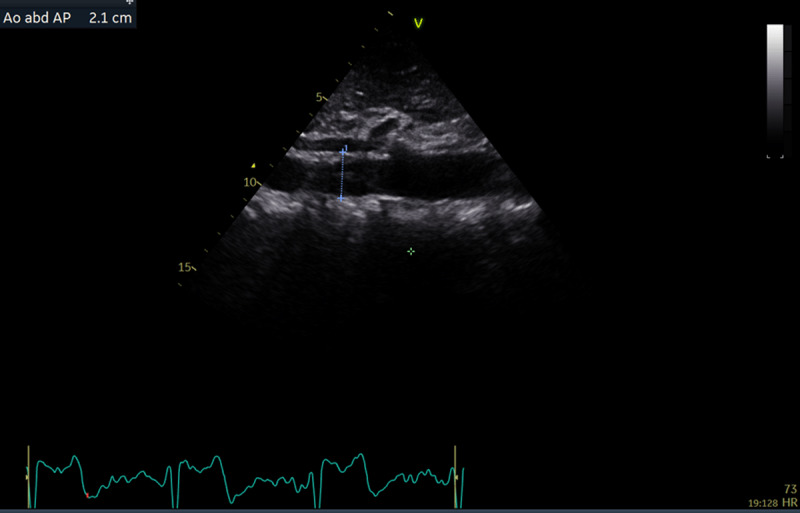

Methods: In 2022, a total of 189 patients with cardiac symptoms visiting the Mnazi Mmoja Referral Hospital (MMH) in Zanzibar underwent standard transthoracic echocardiography (TTE). Demographics and clinical data were recorded. AA diameter was routinely assessed in 137 patients. AA was measured by the leading-edge-to-leading-edge method from a longitudinal plane, and AAA was defined as an AA diameter of ≥3.0 cm. SPSS version 29.0 was used for data analysis. The prevalence of AAA was estimated as the number of AAA cases divided by the number of all screened subjects. Correlates of AA diameter were tested in univariate and multivariate linear regression analyses.

Results: AA could be visualized in 128 (93.4%) patients (43% of men and 57% of women). The mean age was 54.4 ± 15.9 years. The mean AA diameter was 2.1 ± 0.3 cm in the entire study population and was significantly greater in men than women (2.2 ± 0.3 vs 2.1 ± 0.3 cm, p = 0.005) and in individuals aged ≥60 years than those aged <60 years (2.3 ± 0.3 vs 2.1 ± 0.3 cm, p = 0.003). The prevalence of AAA was 1.6%. In a multivariate linear regression analysis, higher age, male gender, atrial fibrillation and left ventricular (LV) mass were independent correlates of greater AA diameter, adjusted for clinic systolic blood pressure, ascending aortic diameter and LV ejection fraction (multiple R2 = 0.38, p < 0.001).